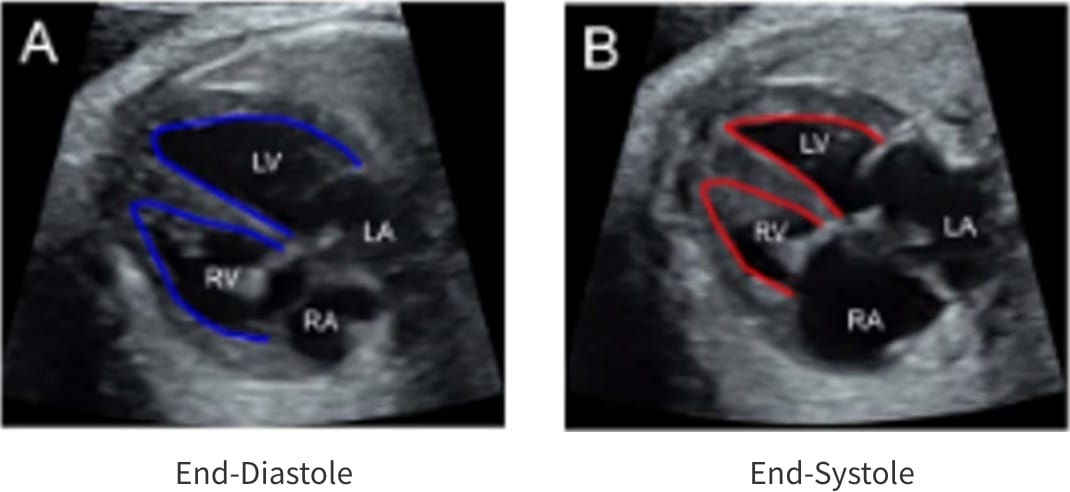

Fetal HQ®はSpeckle-Tracking法を用いて胎児心室壁の運動を解析する方法です。Speckle-Tracking法とは心筋の断層エコー画像上の小斑点(speckle)を追跡し心筋局所の機能を解析する方法で、成人の心臓超音波検査でも用いられています。一回数秒の動画の保存で複数の心機能が同時に評価できる新しい検査法です。

Fractional shortning

(拡張末期径−収縮末期径)/拡張末期径×100で表され、短軸で収縮能を評価する。SegmentごとにFSを算出できる。

Fractional area change

(拡張末期面積–収縮末期面積)/拡張末期面積×100で表され、面積で収縮能を評価する。

Fetal HQの臨床における活用はまだ限定的です。当院では先天性心疾患の胎児や、双胎間輸血症候群・胎児胸水・胎児貧血といった胎児治療が必要な胎児の心機能を評価するために、従来用いられている心機能の評価項目に加え、Fetal HQを用いて心エコー検査を行っています。データを積み上げ、Fetal HQの活用の幅を広げていきます。

胎児心不全の一例:著明な心拡大と収縮機能低下を認める